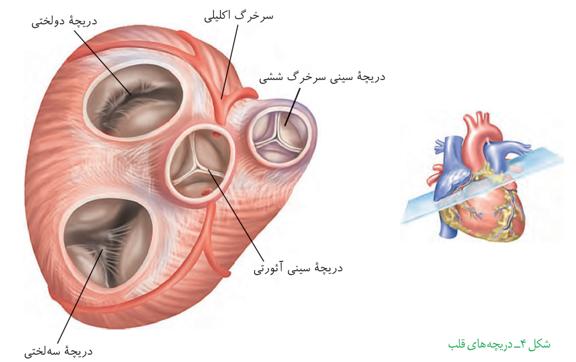

به هر کلیه، یک سرخرگ وارد میشود. انشعابات این سرخرگ از فواصل بین هرمها عبور میکند و در بخش قشری به سرخرگهای کوچکتری تقسیم میشود. انشعاب انتهایی این سرخرگها، سرخرگ آوران نامیده میشود. سرخرگ آوران در کپسول بومن، شبکه مویرگی کلافک را میسازد. خون از طریق سرخرگ آوران به کلافک وارد میشود و از طریق سرخرگ وابران آن را ترک میکند.

سرخرگ وابران در اطراف لولههای پیچخورده و قوس هنله، شبکه مویرگی دورِ لولهای را میسازد. این مویرگها به یکدیگر میپیوندند و سیاهرگهای کوچکی بهوجود میآورند که پس از عبور از فواصل بین هرمها سرانجام سیاهرگ کلیه را میسازند. این سیاهرگ، خون را از کلیه بیرون میبرد.